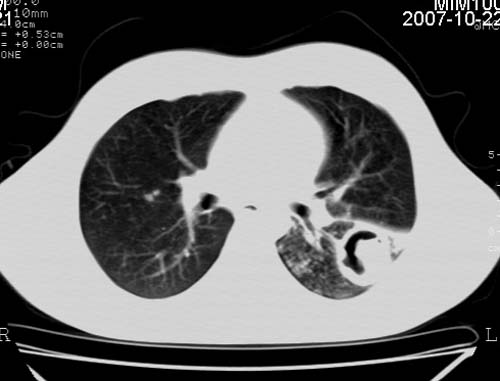

男,21岁,咳嗽、胸闷、乏力伴多汗二十余日、无明显发烧。患者一般情况好,为初三学生。

双肺继发性肺结核伴左侧空洞形成!不除外合并霉菌感染!(双肺多发病灶,左侧病灶形成空洞,并空洞内见壁结节。建议改变体位,观察空洞内结节情况,以便排除霉菌感染!)

结核并支气管播散

左下肺实变能给出合理解释吗?